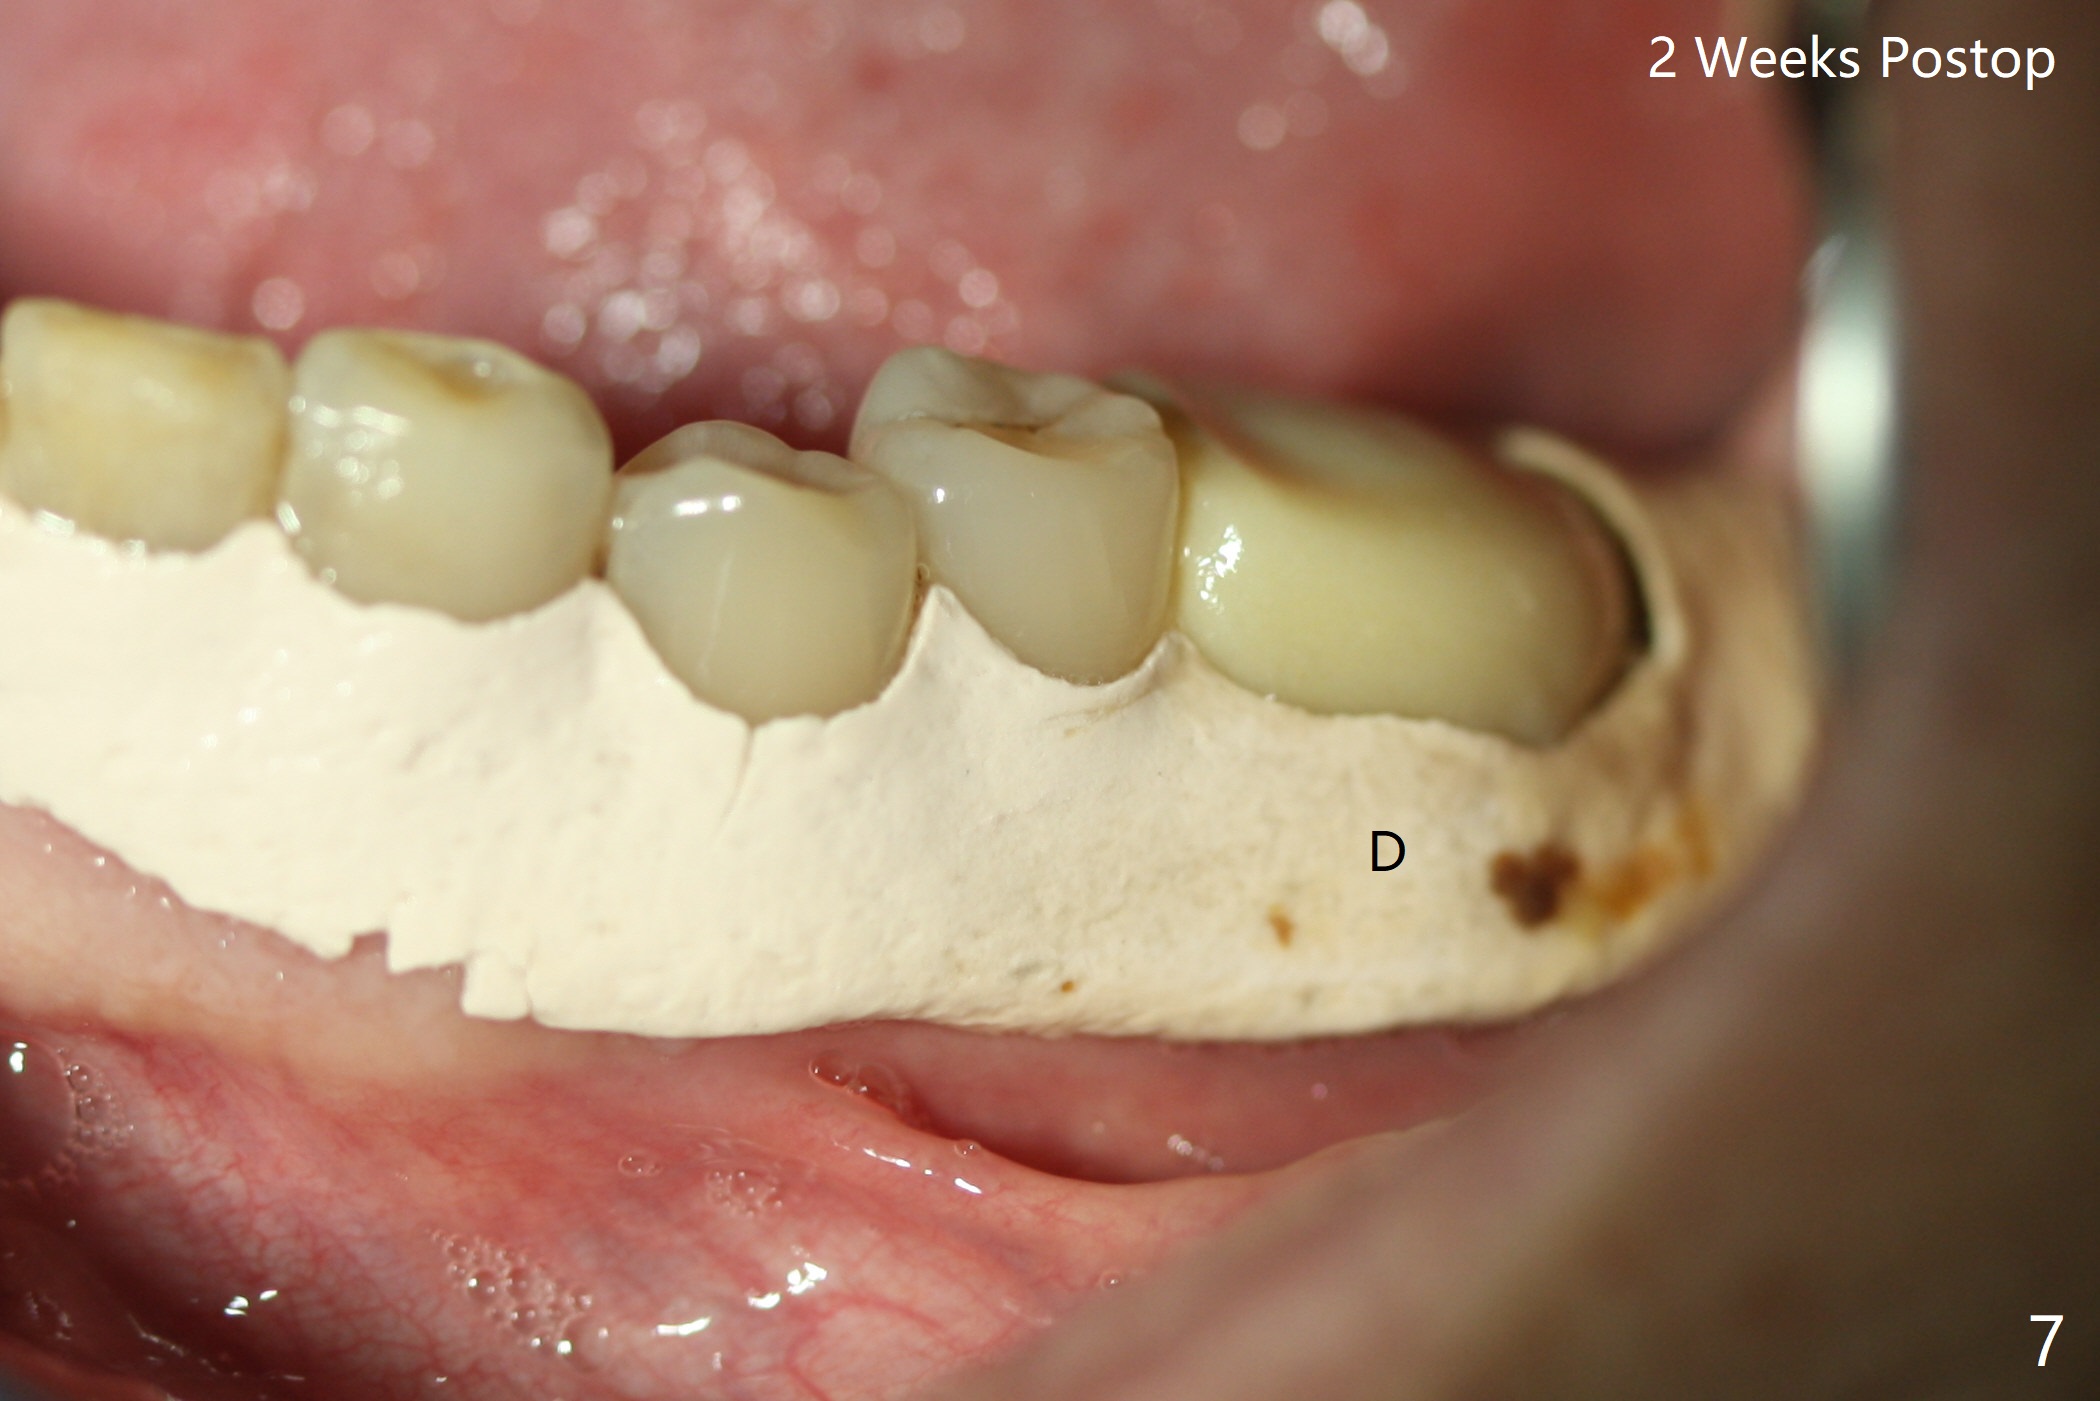

When the patient returns for #19 extraction (Fig.1), there is no 5x10 mm implant available. In fact the smaller one (4.5x10 mm) is able to achieve insertion torque >60 Ncm with more room for autogenous bone/allograft horizontally (Fig.2 *). After insertion of a definitive abutment (6.5x5.5(4) mm), more allograft is placed coronally (Fig.3 *). The gingiva that was between the mesial and distal roots before extraction (Fig.1 *) is transferred distal (Fig.4.5 *). An immediate provisional (Fig.6 P) is fabricated to close the socket opening, followed by periodontal dressing (data not shown). The latter is partially detached 2 weeks postop (Fig.7 D). When it is removed, some of possibly collagen plug is exposed distobuccally (Fig.8). When the plug is removed, some of the bone graft (Fig.9 *) is exposed distal to the provisional (P). New periodontal dressing is applied to keep the exposed graft in place. There is no apparent thread exposure 4 months postop (Fig.10). The abutment is loose 4 months post cementation, probably related to unfavorable crown/implant ratio; but when the abutment is retightened, there is a gap between it and the implant (Fig. 11 >). After relieving the proximal contact of the crown, the abutment is retightened one more time with the same gap (Fig.12 >). In fact the latter is present previously. A narrower abutment with longer cuff appears to be completely seated, probably avoiding contact with the regenerated crestal bone (Fig.13 *). If the new crown gets loose, bury a driver inside the abutment.